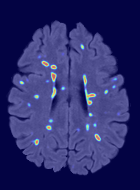

Patch size is another important parameter of the network. In computer vision applications such as object detection, usually a whole 2D image is used as a feature. However, full 3D medical images can not typically be used because of memory limitations. Fig. 4 shows examples of lesion memberships obtained with different sized 2D patches. As the patch sizes increases, the false positives that are mostly observed in the cortex tend to decrease. Fig. 5 shows a plot of Dice and LFPR with various patch sizes, ordered from left to right according to their increasing size. Note that smaller patches ( to ) produced significantly lower Dice and higher LFPR compared to other patches (), as seen from the memberships in Fig. 4. Also some of the highest Dice and lowest LFPR were observed for patches with large in-plane size, i.e., , , and . It was observed in Fig. 5 that there is no significant difference between Dice coefficients for , , or , but LFPR of both and are significantly lower than that of (). We chose as the optimal patch size. Other choices of smaller and patches (not shown) yielded worse results. Note that although training was performed with different patch sizes, the memberships were generated slice by slice, as the trained model consisted only of convolutions and did not need any information about patch sizes.